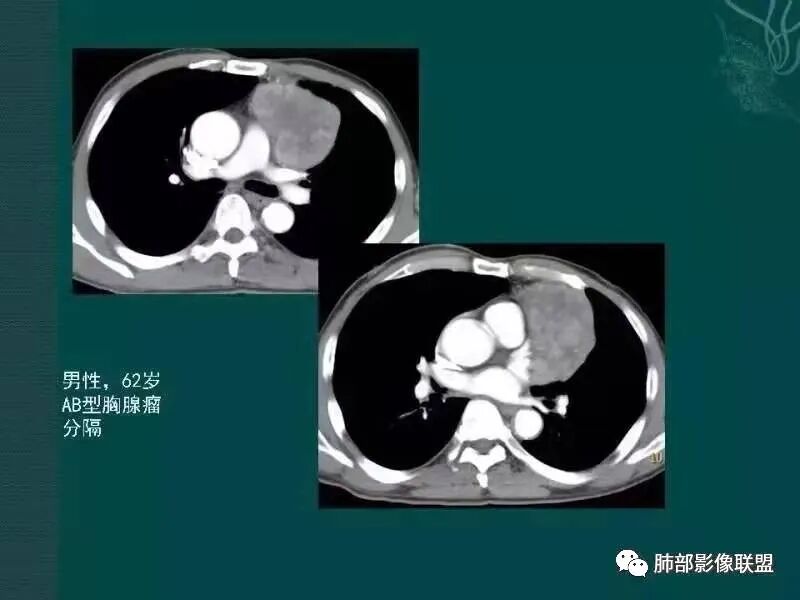

分叶,分隔,AB型胸腺瘤

肿块边界清楚,低密度纤维间隔,未见侵犯转移及增大淋巴结,多见于胸腺瘤AB型